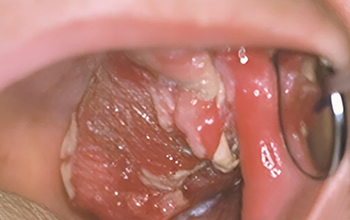

Fig. 03 : tumeur ulcéro-bourgeonnante du bord latéral de la langue.